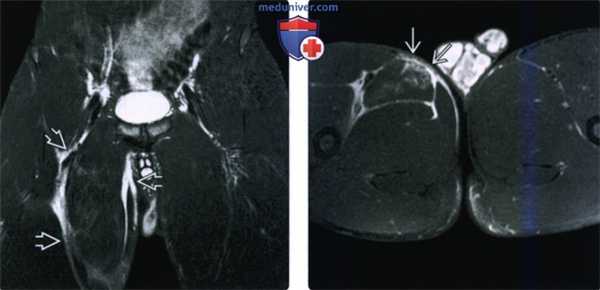

(Слева) МРТ, STIR, коронарный срез: у профессионального хоккеиста с ноющей болью в паху определяется околомышечный отек всего ложа приводящих мышц, что указывает на повторное растяжение.

(Справа) МРТ Т2ВИ, режим подавления сигнала от жира, аксиальный срез: у этого же пациента определяется отсутствие дифференцировки переднемедиальной поверхности оболочки длинной приводящей мышцы. Было выполнено оперативное лечение, поскольку часть длинной приводящей мышцы выпячивалась через эпимизий, что характерно для синдрома бейсбольного питчера/хоккейного вратаря.5. МРТ при травме приводящих мышцы бедра: